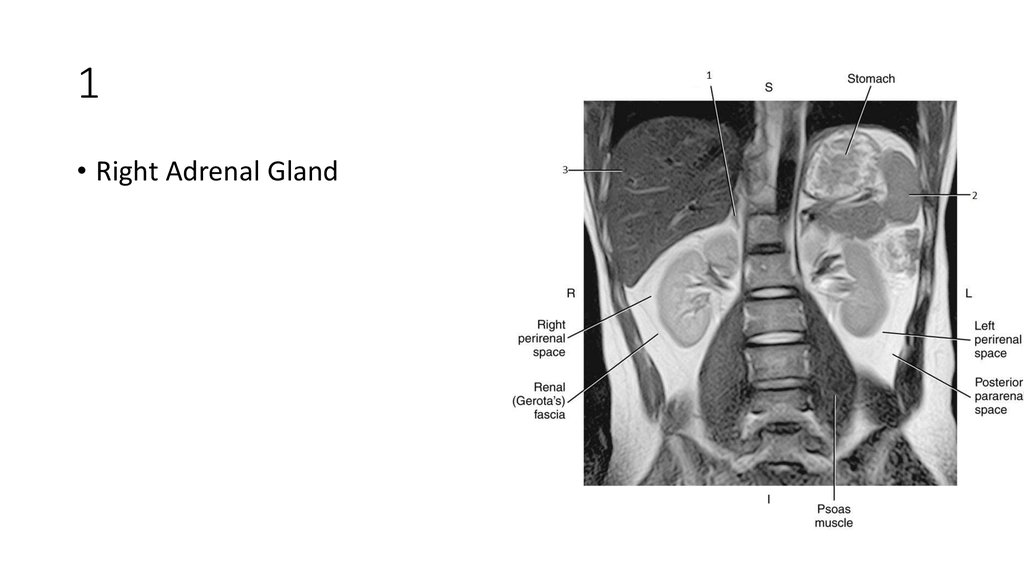

10. 1

11. 1

• Right Adrenal Gland

12. 2

13. 2

• Spleen

14. 3

15. 3

• Liver